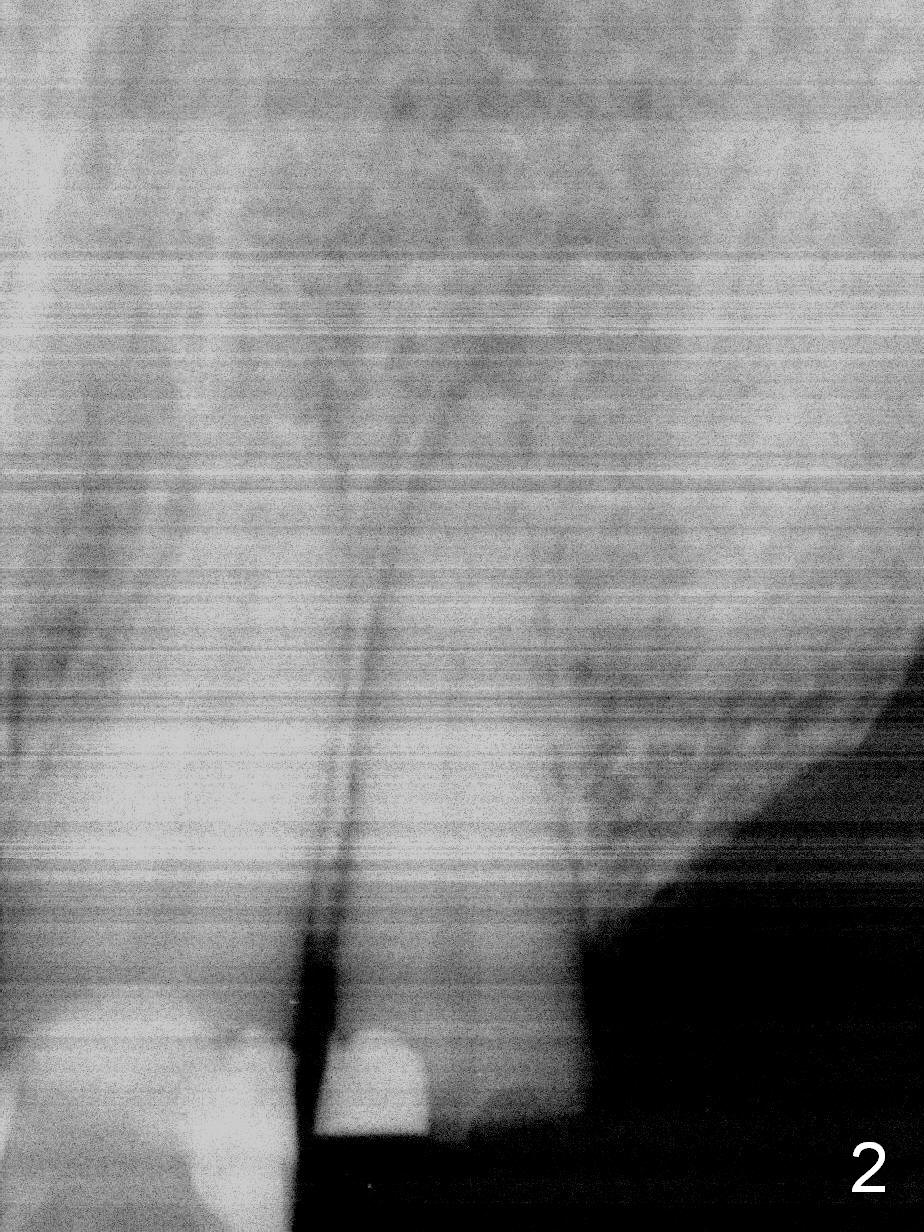

How to avoid apparent iatrogenic damage to the neighboring root? Preop PA shows approximation of these roots (Fig.2). Unfortunately the initial osteotomy is too mesial (Fig.3), which is unnoticed. When a 4.5x17 mm implant is placed, there is distal gap (Fig.4 <), while the mesial one is closed.

When the two neighboring roots are close to each other, start the osteotomy distally (Fig.5,6) particularly for the site at the distal end.